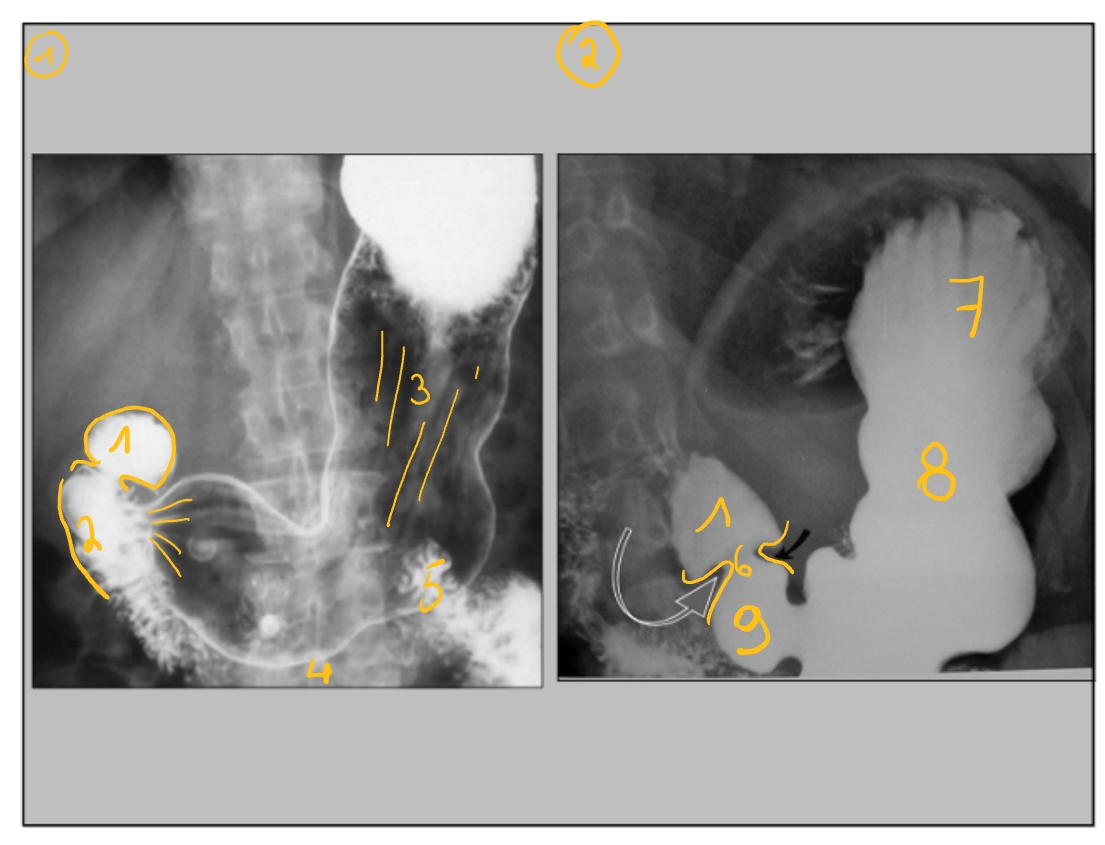

BaSO4 = bariumsulfaat (opdrinken)

zwaar atoom → neemt veel röntgenstralen op → kleurt wit

FOTO 1: dubbelcontrast (want veel lucht in maag)

FOTO 2: enkelcontrast (want weinig lucht in maag)

bulbus duodeni

(op moment dat die samentrekt)

pars descendens duodeni

rugae (maagplooien)

pars transversa duodeni

pars ascendens duodeni

m. pylorus

(constante, geen peristaltiek)

fundus

corpus

antrum